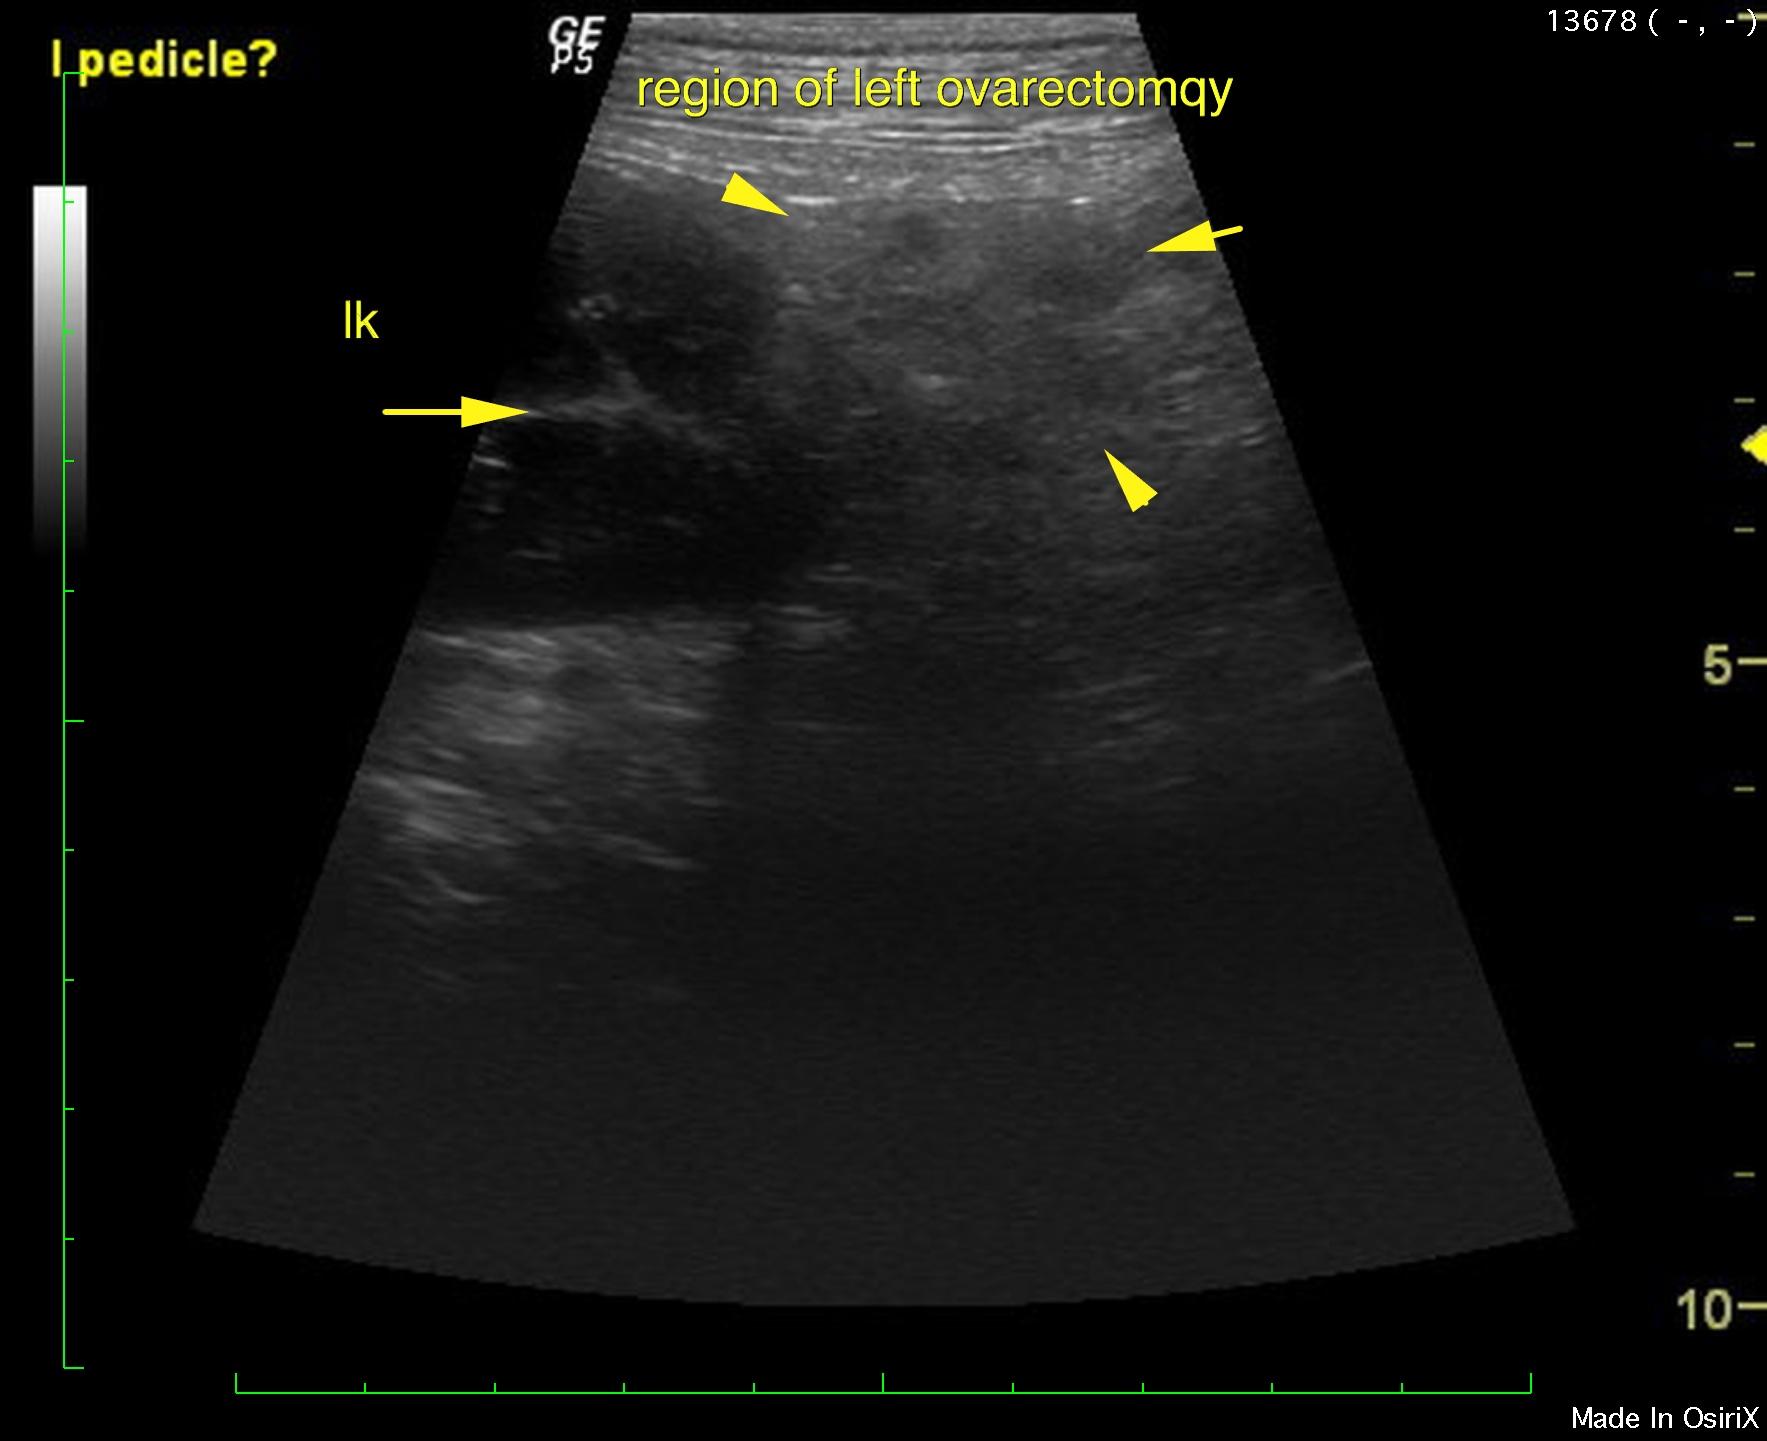

An 11-year-old FS Cane Corso dog was presented post ovariohysterectomy for evaluation of anorexia and an incision site painful seroma that was dripping serosanguinous fluid. Fluid cytology showed the presence of neutrophils.